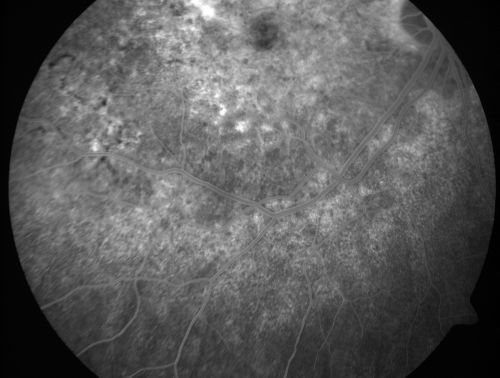

Basal Laminar Drusen - Cuticular Drusen - Equatorial Drusen - 70 Year Old Woman

70 year old woman has had macular drusen since her thirties and she said her sister has a similar problem.  Recently the vision in the left eye has substantially declined. OD 20/16, OS 10/200.